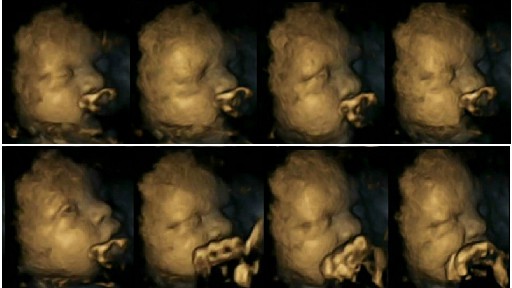

สำนักข่าวต่างประเทศ ได้รายงานผลการวิจัยของ Dr Nadja Reissland จากมหาวิทยาลัยเดอรัม (Durham University) เกี่ยวกับผลกระทบของการสูบบุหรี่ในขณะตั้งครรภ์ พร้อมกับเผย ภาพอัลตราซาวน์ 4 มิติ หรือ 4D ที่แสดงถึงภาพของทารกในครรภ์ที่มีลักษณะการเจริญเติบโต รวมไปถึงการหายใจที่ผิดปกติ และพบว่ามีจำนวนหลายรายถึงขั้นเสียชีวิตภายในครรภ์ไปเลยก็มี

ทั้งนี้นักวิจัยมีความเชื่อว่า หากมีการเปิดเผยข้อมูลเกี่ยวกับผลกระทบจากการสูบบุหรี่หรืออยู่ใกล้ควันบุหรี่ในขณะกำลังตั้งครรภ์ อาจช่วยสร้างแรงบันดาลให้ให้หญิงสาวเหล่านี้ได้ตัดสินใจเลิกสูบบุหรี่อย่างจริงจังเสียที

ภาพ 4D ของลูกน้อยที่แม่ไม่สูบบุหรี่